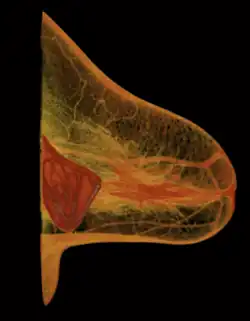

Implant rupture visualized by breast computed tomography

Because a breast implant is a Class III medical device of limited product-life, the principal rupture-rate factors are its age and design; nonetheless, a breast implant device can retain its mechanical integrity for decades in a woman's body.[44] When a saline breast implant ruptures, leaks, and empties, it quickly deflates, and thus can be readily explanted (surgically removed). In some cases, saline implant rupture can result in an infection due to bacteria or mold that had been within the implant, though this is uncommon.[45] The follow-up report, Natrelle Saline-filled Breast Implants: a Prospective 10-year Study (2009) indicated rupture-deflation rates of 3–5 per cent at 3-years post-implantation, and 7–10 per cent rupture-deflation rates at 10-years post-implantation.[46] In a study of his 4761 augmentation mammaplasty patients, Eisenberg reported that overfilling saline breast implants 10-13% significantly reduced the rupture-deflation rate to 1.83% at 8-years post-implantation.[47]

A breast implant failure: the parts of a surgically explanted breast implant are the red, fibrous capsule (left), the ruptured silicone implant (center), and the transparent filler-gel that leaked with the capsule (right).

When a silicone breast implant ruptures it usually does not deflate, yet the filler gel does leak from it, which can migrate to the implant pocket; therefore, an intracapsular rupture (in-capsule leak) can become an extracapsular rupture (out-of-capsule leak), and each occurrence is resolved by explantation. Although the leaked silicone filler-gel can migrate from the chest tissues to elsewhere in the woman's body, most clinical complications are limited to the breast and armpit areas, usually manifested as granulomas (inflammatory nodules) and axillary lymphadenopathy (enlarged lymph glands in the armpit area).[48][49][50]